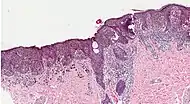

Melanoma in skin biopsy with H&E stain – this case may represent superficial spreading melanoma.

| 1. | Superficial spreading melanoma | Melanoma cells with nest formation along the dermo-epidermal junction. | 70% | ![]() |

![]() |